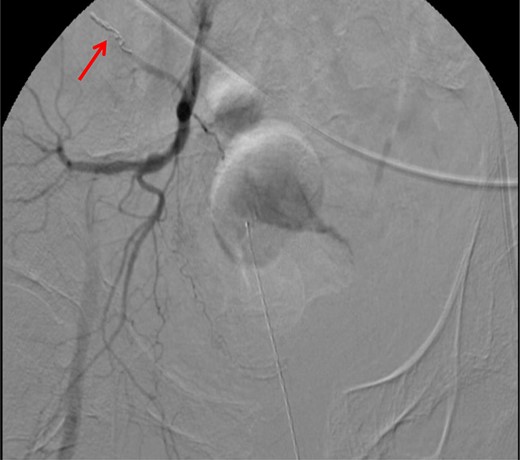

CT abdomen/pelvis with contrast was performed and a blush of contrast was noted posterior to the right pubic bone. Prior to taking patient for exploratory surgery, he was transferred to the interventional radiology suite where a pelvic angiogram was performed revealing an abnormal blush localized to the distal branches of the right iliolumbar artery (Fig. 2). Delayed phase of the angiogram demonstrated early venous filling consistent with a traumatic arteriovenous fistula which was embolized with 300–500 µ of embospheres and three 3 × 2 microcoils (Figs 3 and 4).

CT angiogram demonstrating microcoil embolization of AV fistula.